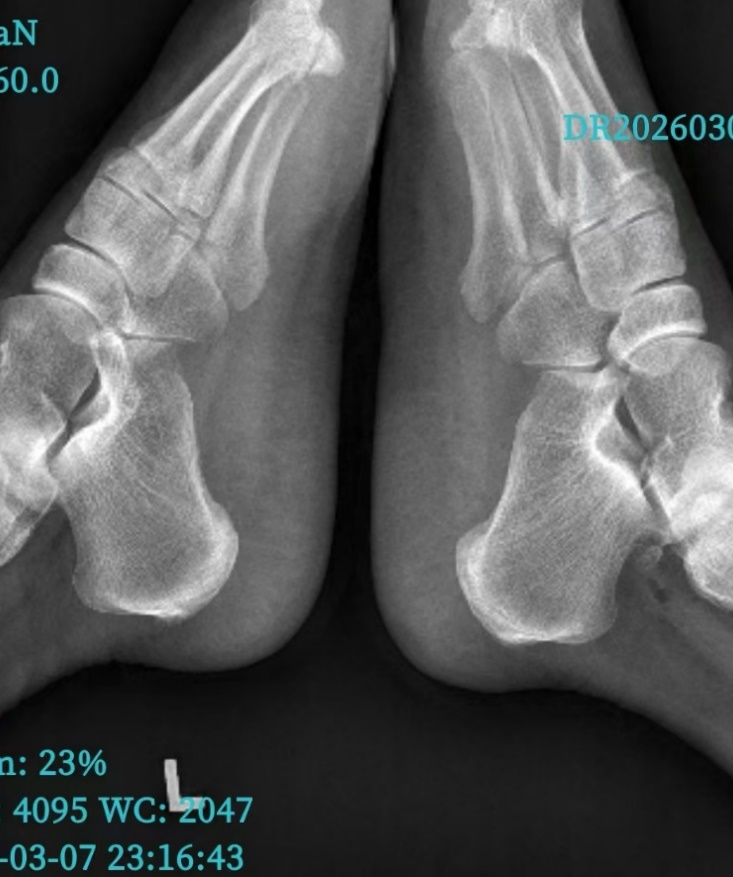

术后双跟骨骨刺完整切除

入院后骨一科团队对其进行了必要的术前检查,结合患者病情,由庞涛副主任医师创新性地实施了关节镜下跟骨骨刺切除并足底筋膜松解术,手术效果满意,病人康复出院。